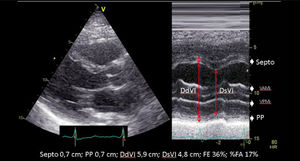

| En presencia de alteraciones segmentarias de la contractilidad, necrosis previa, ventrículos esféricos o presencia de asincronía su utilidad queda muy limitada. La gran resolución temporal del modo M, junto con la ecocardiografía 2D con mejor resolución espacial, nos permitirá la evaluación de los diámetros de la cavidad ventricular realizando cortes en modo-M dirigidos por ecocardiografía 2D. Evitando la oblicuidad. | ||

| A.1. Fracción de eyección ventricular izquierda (FEVI) (Teichholz) | ||

| Aunque es un parámetro que se sigue utilizando en la práctica clínica, se basa en el supuesto que la forma geométrica del ventrículo izquierdo es fija (elipsoide alargado), lo cual no es aplicable en numerosas patologías cardiacas, no siendo recomendada su utilización en caso de trastorno de motilidad segmentaria, ventrículos muy dilatados, asincronía ventricular, etc. | ||

| A.2. Fracción de acortamiento (FA) | ||

| Se trata de un parámetro subrogado de la FE (Teichholz) en la que se valora los DtTDVI y DtTSVI. Presenta las mismas limitaciones que las comentadas en la estimación de la FEVI por Teichholz. | ||